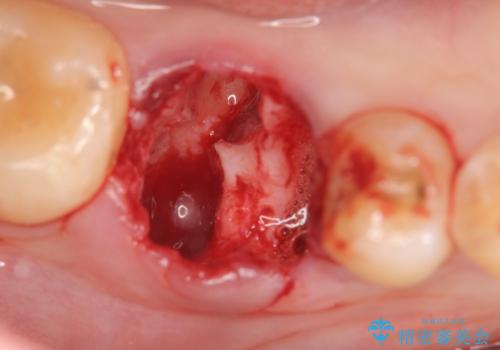

- 虫歯を数年放置した結果、痛みがひどくなり治療を希望され来院されました。

根だけ残った歯は、破折があり急性の炎症が認められ抜歯が必要な状態です。

抜歯後は、前後の歯を削らずにしっかりと咬合力を回復できるインプラント治療を選択されました。